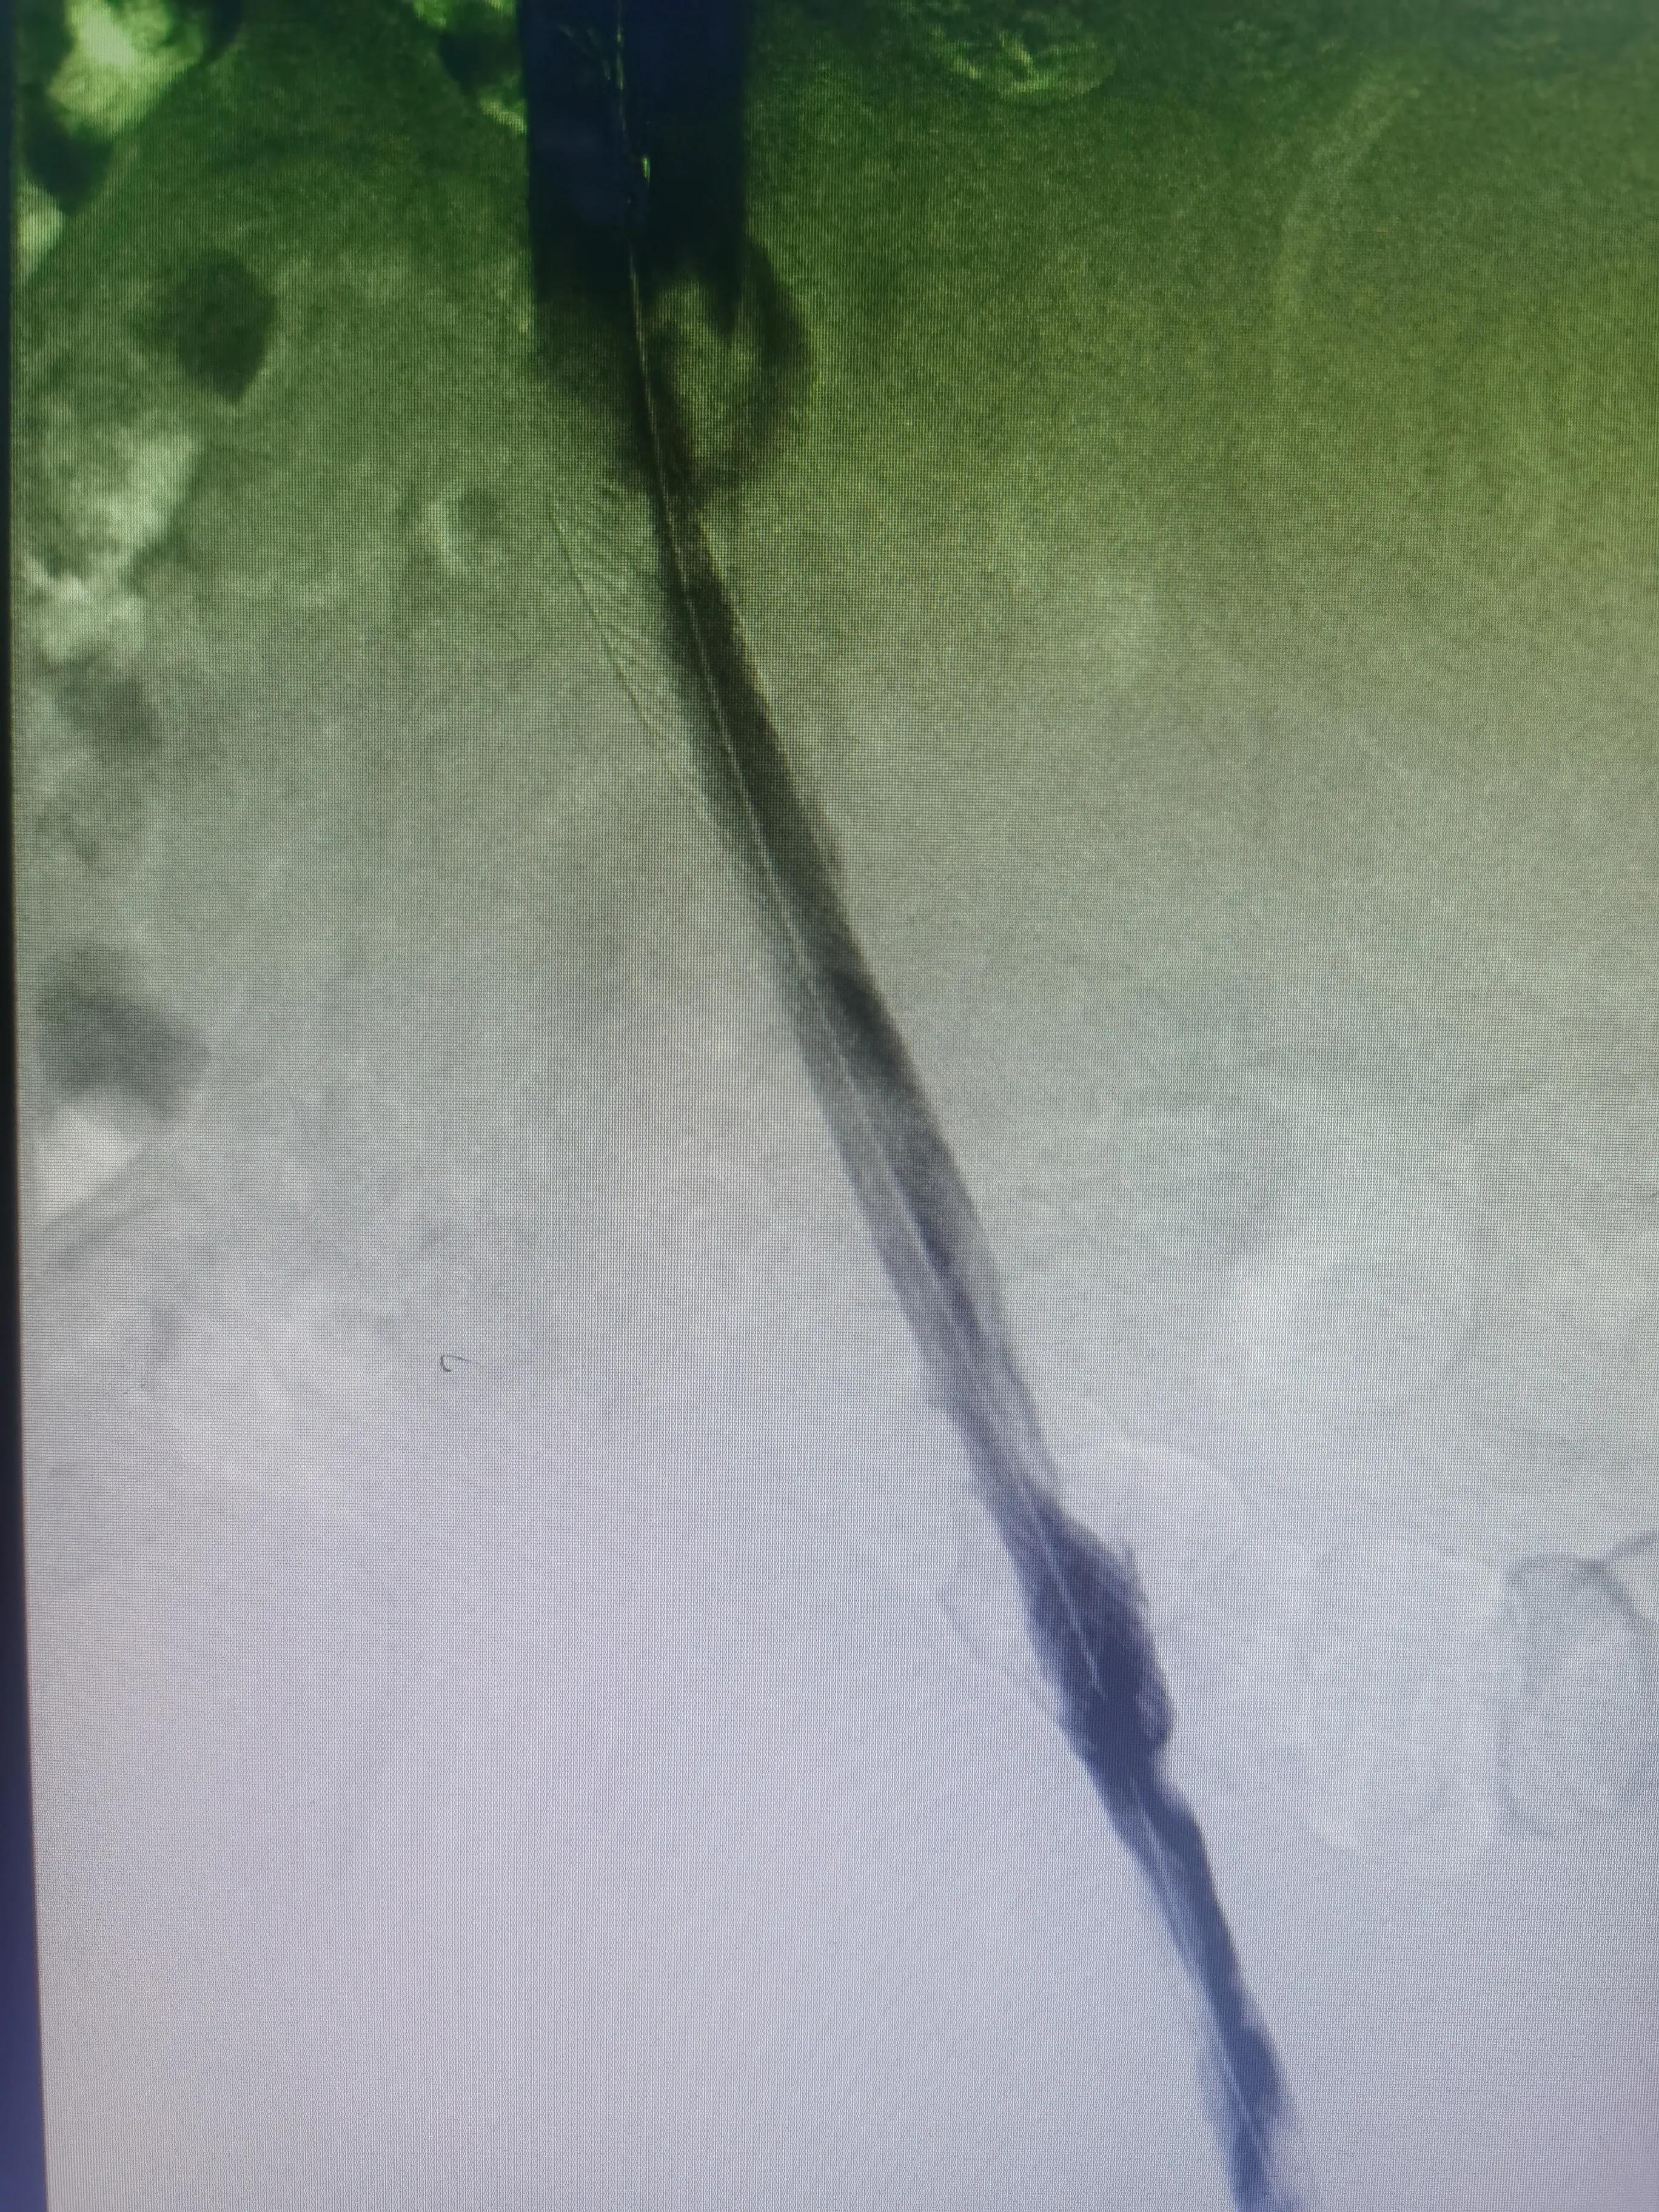

答:这个就需要根据患者自身情况制定个性化治疗策略,主要策略为:①保守抗凝治疗:②系统溶栓治疗;③导管接触性溶栓治疗;④机械性血栓清楚治疗;⑤必要时球囊扩张和支架植入治疗;⑥急危重症病人需切开取栓治疗等。

术前髂静脉闭塞